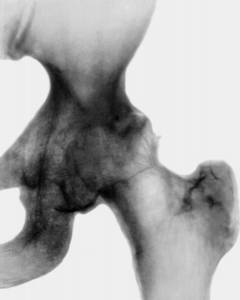

Рентгенологическая диагностика дисплазии тазобедренного сустава

У детей младшего возраста пока еще не произошло окостенение некоторых частей бедренной и тазовой костей. На их месте находятся хрящи, которые не видны на рентгеновских снимках. Поэтому для того, чтобы оценить правильность конфигурации анатомических структур тазобедренного сустава, применяются специальные схемы. Делают снимки в прямой проекции (анфас), на которых проводят условные вспомогательные линии.

Дополнительные линии, которые помогают в диагностике дисплазии тазобедренного сустава по рентгенограммам:

• срединная линия – вертикальная линия, которая проходит через середину крестца;

• линия Хильгенрейнера – горизонтальная линия, которая проводится через самые нижние точки подвздошных костей;

• линия Перкина – вертикальная линия, которая проходит через верхненаружный край вертлужной впадины справа и слева;

• линия Шентона – это линия, которая мысленно продолжает край запирательного отверстия тазовой кости и шейки бедренной кости.

Важный показатель состояния тазобедренного сустава у детей младшего возраста, который определяют на рентгенограммах – ацетабулярный угол. Это угол, образованный линией Хильгенрейнера и касательной линией, проведенной через край вертлужной впадины.

Нормальные показатели ацетабулярного угла у детей разных возрастов:

• у новорожденных – 25 - 29°;

• 1 год жизни – 18,5°(у мальчиков) - 20°(у девочек);

• 5 лет - 15° у обоих полов.

Величина h.

Величина h – это еще один важный показатель, который характеризует вертикальное смещение головки бедра по отношению к тазовым костям. Он равен расстоянию от линии Хильгенрейнера до середины головки бедра. В норме у детей младшего возраста величина h составляет 9 – 12 мм. На наличие дисплазии указывает увеличение или асимметрия.

Величина d.

Это показатель, который характеризует смещение головки бедренной кости кнаружи от суставной впадины. Он равен расстоянию от дна суставной впадины до вертикальной линии h.